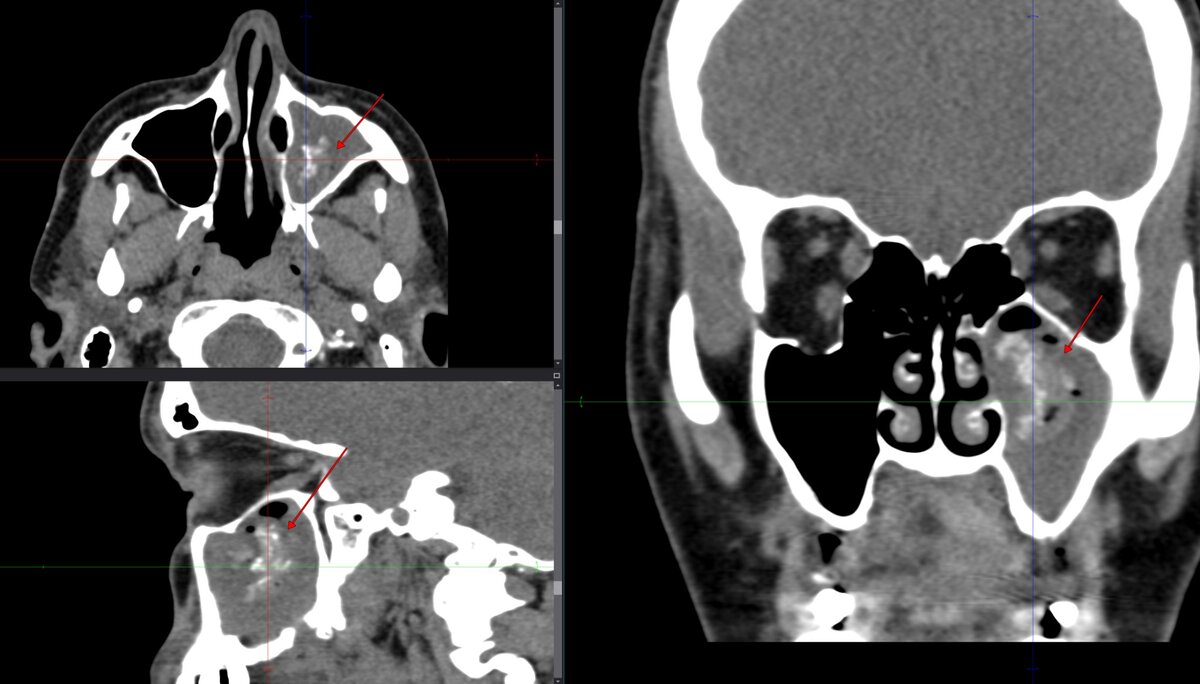

При обследовании методом МСКТ выявлено: субтотальное нарушение пневматизации левой верхнечелюстной пазухи за счет неравномерного умеренного утолщения слизистой оболочки (синяя стрелка) /инфильтративного воспалительного генеза, в том числе на уровне устья и инфраорбитальных ячеек/, с наличием патологического субстрата (красная стрелка), неоднородно повышенной плотности /до 190 HU/ в центральных отделах пазухи, неправильной формы, размерами ориентировочно 1,4х2,0х2,4 см. Периостальные изменения по задней стенке (зеленая стрелка) и костный дефект дна левой верхнечелюстной пазухи (белая стрелка). На этом фоне - минимальный экссудативный компонент в пазухе.

Рис. 1. Патологический субстрат (красная стрелка) неоднородной повышенной плотности